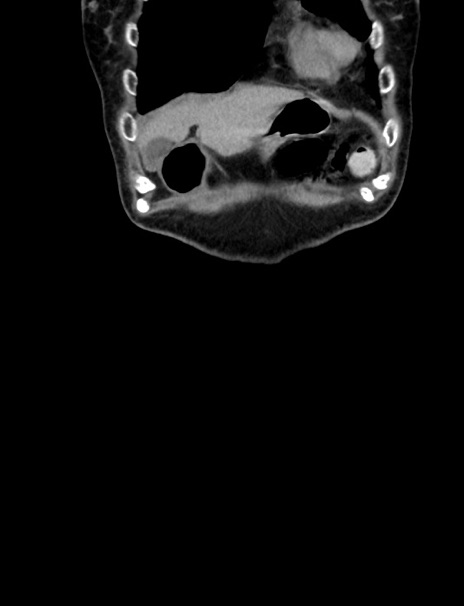

症例33(冠状断像)

【症例】70歳代 女性

【主訴】心窩部痛

【現病歴】延髄病変の精査・加療にて神経内科入院中。本日より心窩部痛あり。

【既往歴】虫垂炎

【身体所見】右下腹部を中心に圧痛と反跳痛あり。

【データ】WBC 10900、CRP 0.02